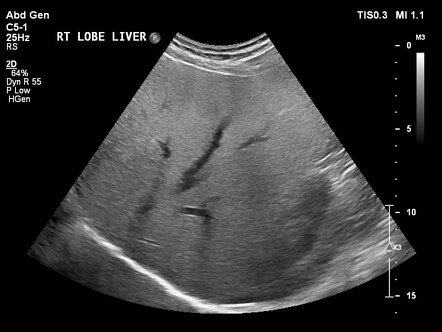

Панельные тесты на гепатит, которые измеряют количество вирусного гепатита в крови, также могут быть полезны в некоторых случаях. Визуализирующие методы (УЗИ печени и др.) могут показать жировую болезнь печени. Врачи могут использовать следующие методы для получения изображения печени:

• ультразвуковое исследование

Однако эти методики не могут конкретно диагностировать стеатоз.